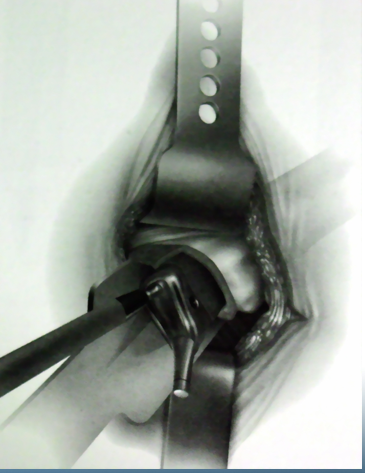

沿阔筋膜纤维方向切开扩筋膜大粗隆顶点臀中肌前1/3处沿纤维方向分离臀中肌

横形切开臀小肌2cm

沿大粗隆前缘切开臀中肌腱和臀小肌

切除关节囊髋关节内收、屈曲、外旋位脱位

准备髋臼

准备股骨髓腔

缝合切开之臀小肌和臀中肌